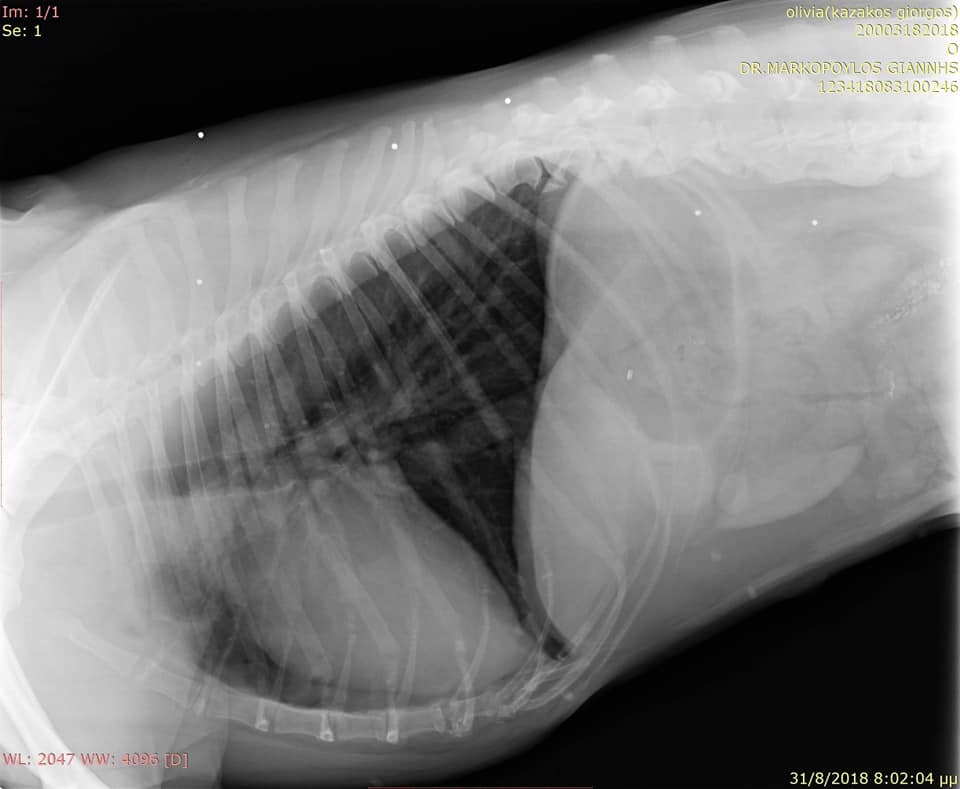

Στο κτηνιατρείο του Γιάννη Μαρκόπουλου στην Κυπαρισσία μεταφέρθηκε στις 31 Αυγούστου ο σκύλος, ο οποίος πυροβολήθηκε με καραμπίνα στα Φιλιατρά Μεσσηνίας από κάτοικο της περιοχής.

FiliatraMessiniasPyrovolimenosSkylosAktinografia 1Η ακτινογραφία έδειξε τα σκάγια στο σώμα του σκύλου.

FiliatraMessiniasPyrovolimenosSkylosAktinografia 2